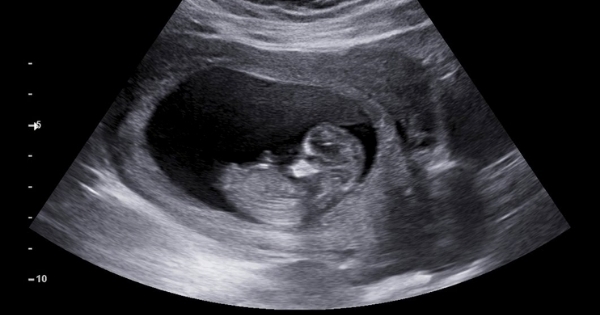

▲胎兒踢掉避孕器,誰也檔不住生下來。(示意圖/shutterstock達志影像)

「一掃,懷孕了!而且寶寶看起來已經20週,

我就跟媽媽說,恭喜,42歲還懷孕了這樣。」